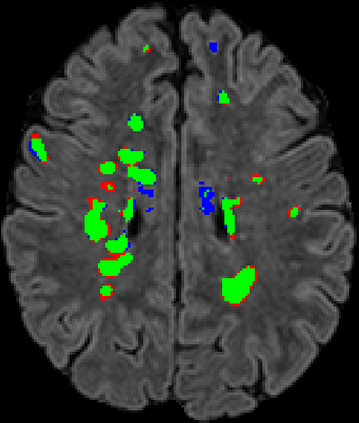

Recently, segmentation methods based on Convolutional Neural Networks (CNNs) showed promising performance in automatic Multiple Sclerosis (MS) lesions segmentation. These techniques have even outperformed human experts in controlled evaluation conditions such as Longitudinal MS Lesion Segmentation Challenge (ISBI Challenge). However state-of-the-art approaches trained to perform well on highly-controlled datasets fail to generalize on clinical data from unseen datasets. Instead of proposing another improvement of the segmentation accuracy, we propose a novel method robust to domain shift and performing well on unseen datasets, called DeepLesionBrain (DLB). This generalization property results from three main contributions. First, DLB is based on a large group of compact 3D CNNs. This spatially distributed strategy ensures a robust prediction despite the risk of generalization failure of some individual networks. Second, DLB includes a new image quality data augmentation to reduce dependency to training data specificity (e.g., acquisition protocol). Finally, to learn a more generalizable representation of MS lesions, we propose a hierarchical specialization learning (HSL). HSL is performed by pre-training a generic network over the whole brain, before using its weights as initialization to locally specialized networks. By this end, DLB learns both generic features extracted at global image level and specific features extracted at local image level. DLB generalization was validated in cross-dataset experiments on MSSEG'16, ISBI challenge, and in-house datasets. During experiments, DLB showed higher segmentation accuracy, better segmentation consistency and greater generalization performance compared to state-of-the-art methods. Therefore, DLB offers a robust framework well-suited for clinical practice.